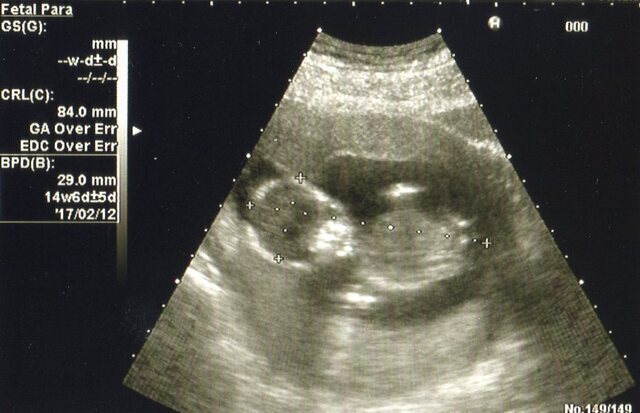

14週1日(14w1d・男の子)|なかこ さん(35歳)

エコー写真撮影時のエピソード:

エコーを主人と一緒に見ながら、説明を受けました。だんだんはっきりと人間の形がわかってきて、まだ週数が浅いのにすごいなぁと感動しました。

なんだか、まん丸い頭に目と口もわかり、お腹もまん丸で、エコー写真なのにすごくかわいいなと感じました。

冷静になって見ると、少しガイコツみたいで怖い?!なんて、思いながらすでに親バカだなぁとにやけて、何度も見返していました。